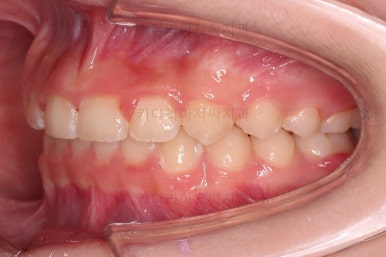

앞니 각도가 매우 좋아졌고요.(옥니 개선) 위 아래 앞니가 덮는 정도도 개선되었어요.(과개교합, 딥바이트)

엉성했던 어금니 맞물림도 매우 좋아졌어요.(앵글씨 2급 부정교합)

특히 옆라인에서 아래턱이 살아나면서 입매가 매우 예뻐졌어요.

부산교정병원 전후사진을 비교해 볼게요.

협조도가 요구되는 장치를 잘 못끼는 바람에 중간에 우여곡절이 있었고 힘든 과정도 있었지만 비교적 만족스러운 치료를 할 수 있었어요.